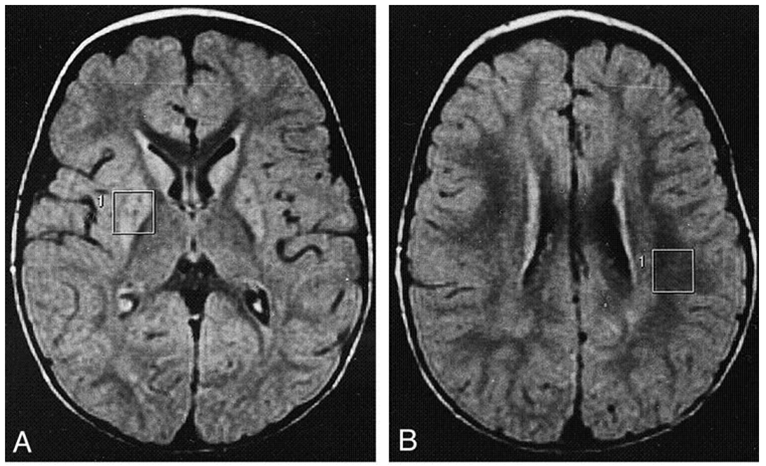

★Leigh syndrome:线粒体病,母系遗传

· 多见于婴幼儿,中枢神经系统病变,智力与运动机能发育障碍,高乳酸血症

★Pyruvate dehydrogenase complex 缺陷

· 严重缺陷为何致死?为什么有高乳酸血症?